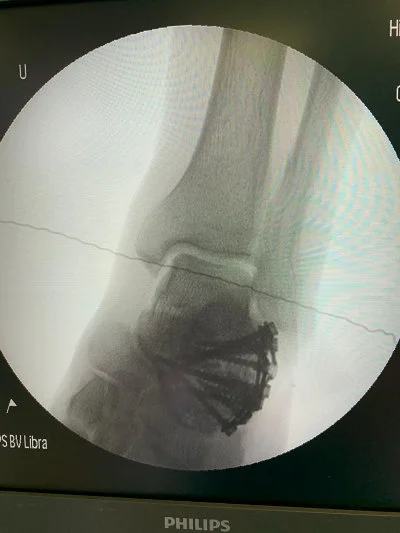

Görüntüleri büyütmek için resmin üstüne tıklayınız.